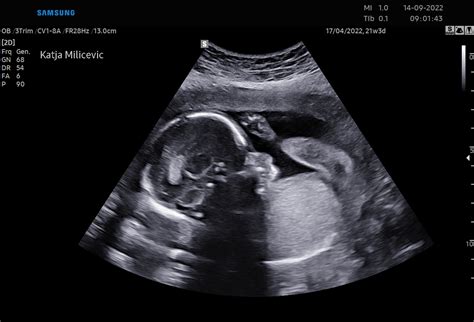

- 20. - 23. teden: Ultrazvočna preiskava za natančno oceno razvoja plodovih organskih sistemov (morfologija ploda). V tem času se lahko spremeni predvideni datum poroda (PDP). Na željo se določi spol otroka. Še vedno se ocenjujejo znaki za kromosomske in druge nepravilnosti. V primeru sumljivih znakov se lahko opravi NIPT test ali diagnostična preiskava - amniocenteza.